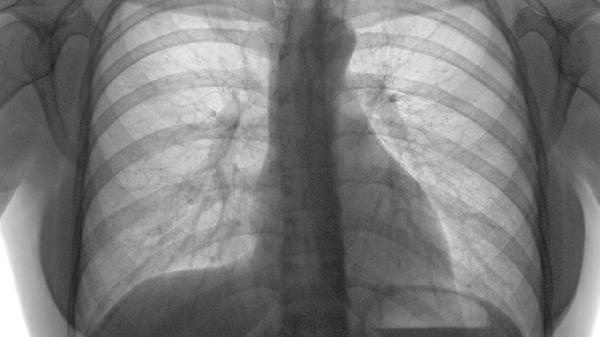

肋软骨炎可能与外伤、慢性劳损、病毒感染、免疫异常、胸椎病变等因素有关,通常表现为胸痛、局部压痛、肿胀等症状。肋软骨炎可通过休息制动、药物治疗、物理治疗等方式缓解。

5、胸椎病变

胸椎小关节紊乱或椎间盘突出可能通过神经反射引发肋软骨牵涉痛,常伴有背部酸胀感。需行脊柱影像学检查,通过手法复位或牵引治疗原发病,可短期使用盐酸乙哌立松片缓解肌肉痉挛。